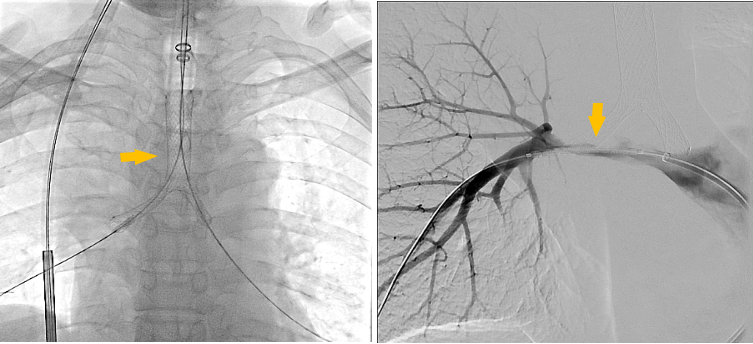

介入手术室里,一场无声的战役打响。麻醉科主任闫华凭借高超技术,成功为患者通气建立安全通路,为手术的实施奠定基石。介入科主任贺光辉带领团队细致操作,将一枚Y形气管支架在X线引导下输送至预定位置后精准释放,原本被肿瘤挤压得只剩一丝缝隙的气道被稳稳地撑开。紧接着一枚肺动脉覆膜支架置入到受压变窄的右肺动脉主干内并准确释放,再次造影,使得右肺动脉血流迅速得到改善。

术前受压变窄的右肺动脉和中央气道